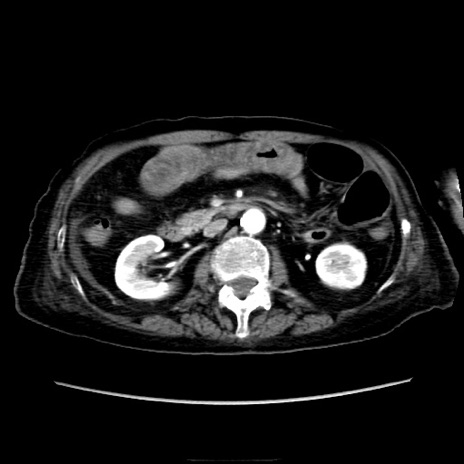

症例40(横断像)

【症例】90歳代女性

【主訴】腹痛・嘔吐

【現病歴】 食欲低下、嘔吐があり昨日他院受診。肺炎と診断され入院となる。入院後より腹部全体に圧痛あり。胃管留置され経過みていたが、症状持続するため、

当院転院となる。

【既往歴】胸椎圧迫骨折、胆石症

【身体所見】腹部:中央に激痛あり、圧痛あり、反跳痛不明

【データ】WBC 17100、CRP 18.82

横断像